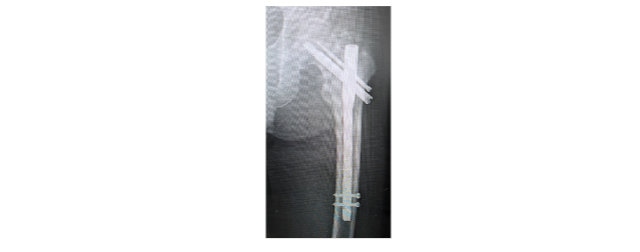

- 大腿骨近位部骨折

大腿骨近位部骨折は、骨粗鬆症で骨がもろくなった高齢者に多発することで有名であり、本邦でも年間10数万人が受傷するといわれています。股関節部(脚の付け根)に痛みがあり、ほとんどの場合、立つことや歩くことができなくなります。

手術しない場合、安静期間中に認知症や廃用萎縮といって動けないうちに運動機能が低下し寝たきりになってしまう可能性が高くなります。手術方法は、骨折型により異なりますが、骨の中に金属を入れたり、人工物に置き換えたりします。当院では、受傷48時間以内に手術を行うことを心掛けており、手術を行うことで翌日から歩行訓練を開始できます。